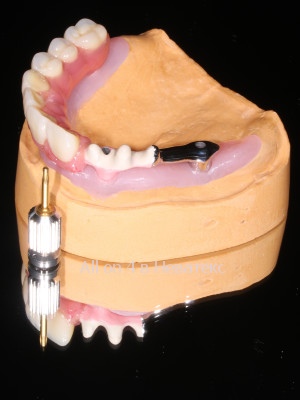

При изготовлении постоянного конструктива(начинки) протеза применяется технологичное литье MESA Magnum H50 с прессованием (Ti)титана 5 Grade. Отдельное и самое важное посещение пациента на 3 й день после операции - примерка гибридной балки гребнки, армирующей базу где распределяется пиковая нагрузка зубов - это и есть *скелет постоянной конструкции и основа привычных жевательных нагрузок.

Керамокомпозито-наполненный диоксидом кремния протез на гибридной балке с титановой основой требует трех примерок после операции All-on-4 / All-on-6 и в отличии от металлопластмассовых адаптационных конструкций не требует перепротезирования

Литая балка в каркасе протеза армирована поясом на титановой основе, что значительно увеличивает прочность конструкции в целом.

Постоянный гибридный керамокомпозито-наполненный протез на ( балке-прототип Nobel Bar> включена в стоимость акции ), армирующей базу протеза, равномерно распределяет выламывающие горизонтальные тризмы, при переходе от адаптационных к постоянным нагрузкам, считается постоянной конструкцией для долгосрочного использования.